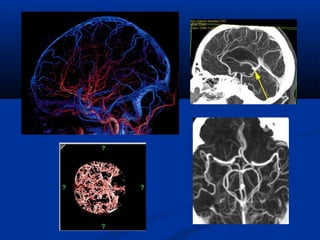

Diffusion Perfusion

Diffusion Tensor MRI

(DTMRI)

Choline vaø lactic acidPHOÅ COÄNG HÖÔÛNG

TÖØ

(SPECTROSCOPY/MRS)